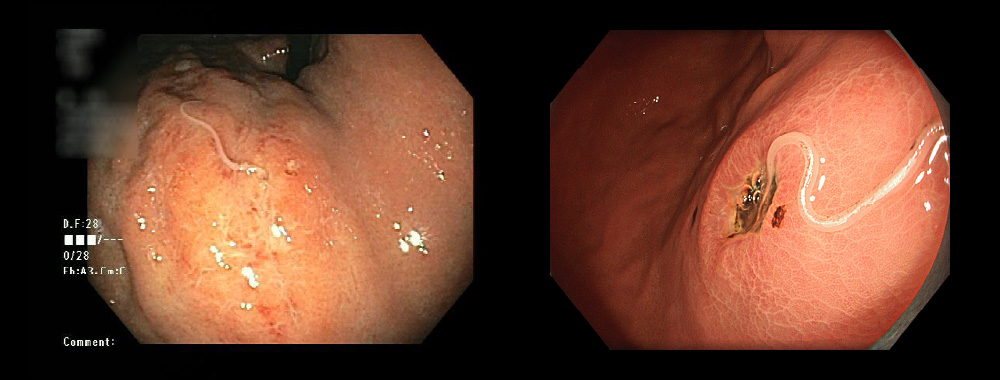

以下は冷や汗を伴う腹痛で受診した患者さんです。魚に生息する虫、アニサキスが原因であり、摘出したところすぐに症状が消失しました。

胃アニサキス

ひどい腹痛で受診され、緊急内視鏡で摘出して軽快されました。